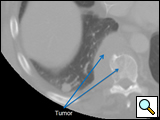

The thoracic spine can be approached through the right or left chest and communication with the spine surgeon is mandatory so that the approach and extent of exposure can be tailored appropriately. In the absence of lateralizing pathology, either a right or left-sided thoracotomy can be used to expose the thoracic spine. As a general rule, the upper thoracic spine (T2-9) is better approached from the right side because of the location of the heart, aortic arch and great vessels. Conversely, in the case of the thoracolumbar spine (T10-L2) a left-sided thoracotomy is preferred to avoid liver retraction. The side of approach must provide maximum exposure to the pathology to be treated. Local factors such as previous thoracotomy, pleurodesis, or infection should also be considered. In general, a right sided approach provides more direct access to the spine, as the mediastinal structures lie to the left of the vertebral bodies. CT and MRI allow for a precise evaluation of the anatomy of the spine pathology and the related intra-thoracic structures (Figures 1a, 1b).